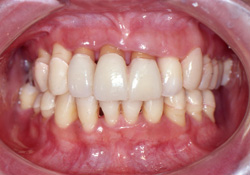

|  			来院理由何件かの歯科医院をまわり、「総義歯」か「インプラント」でしか治せないと言われ芥川歯科にたどり着かれました。

歯周病で困っている「 前歯がとび出し、グラグラ動く 」そうです。

歯周病が原因で、歯並びなど変化した結果、「 前歯がとび出し、グラグラ動く 」 のです。